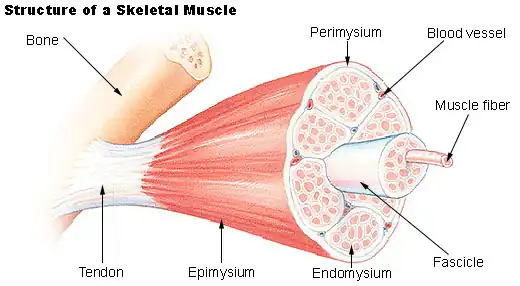

Muscle

Skeletal Muscle

Dense Irregular Connective Tissue has more fibers than ground substance. The fiber type is mainly collagen, and the dominant cells are fibroblasts. Dense Irregular Connective Tissue forms the sheaths of nerves and muscles. Anatomists 'organized fascia' is of this type.

Parallel fibers of collagen. This connective tissue makes up ligaments and tendons

| Muscle | Cells can generate electrical signals, which result in contraction. 'Voluntary' muscle makes up skeletal muscles; Cardiac muscle powers the heart; smooth muscle surrounds hollow organs and tubes. | Muscular tissue does not secrete its own matrix. Skeletal muscle is supported by fibous tissue, and is attached to tendons. | Intestinal Smooth muscle and Cardiac muscle both have cell to cell communication. |